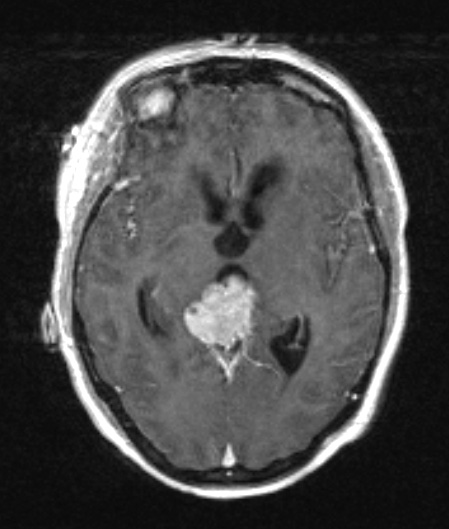

4A2 Pineocytoma (Case 4) T1W - Copy

This T1-weighted image shows prominent enhancement with contrast.